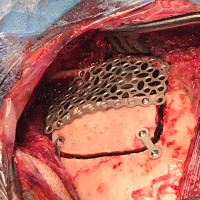

Intraoperative photo demonstrating the operative approach. A right temporal craniotomy has been made and the covering of the brain, the dura mater, is being dissected off of the base of the skull. Orientation: this is the right side of the head; the ear is just off the top of the frame (green star(*)), the nose is to the left, the back of the head the right, and the top of the head is toward the bottom.